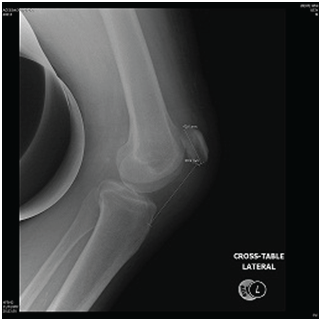

The patient underwent surgical repair of both tendons through a midline knee approach. The left patellar tendon was found avulsed from the bony attachment in the patella. Refreshment of the surface of the distal pole made. Then 2.5 mm drill used to make 3 tunnels. Ethibond suture size 5 used for the repair and augmented with figure of 8 cable. The right quadriceps tendon was repaired by the same steps but without cable augmentation (Figure 4,5). Postoperatively, the patient was kept on bilateral knee immobilizer for 3 weeks on the left knee and 6 weeks on the right knee. After that, extensive physiotherapy and rehabilitation program started. At 10 week postoperatively, the patient is mobilizing full weight bearing using axillary crutches. Active bilateral knee extension restored (Figure 6–8). No complications noted at 6,12 and 18 months follow up.

Figure 4 Post-operative radiographs of the right knee.

Figure 5 Post-operative radiographs of the left knee.